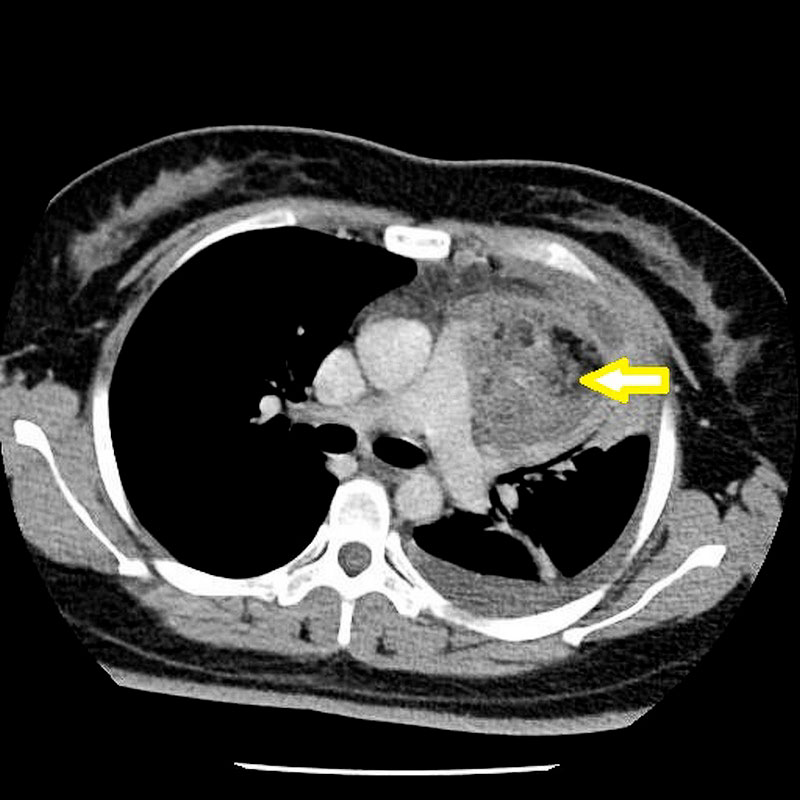

女性手痛延續到肩背,經電腦斷層檢查,前縱膈腔有一顆七公分的畸胎瘤。

二十八歲的張小姐前陣子因為左手痛,陸續到診所看中醫與復健科,但是三個月過去都沒有顯著改善,狀況還愈來愈嚴重,連舉手都有困難。疼痛部位蔓延到肩背,一日更痛到無法離開床上、全身發冷,到醫學中心檢查發現她的胸腔有一顆相當巨大的腫瘤。張小姐因畏懼手術,在處理急性症狀後先行返家,但數天後再次因胸痛、背痛、咳嗽到無法平躺來到台北慈濟醫院。檢查發現,位於前縱膈腔的腫瘤有七公分大,已經壓迫神經,胸腔外科洪嘉聰醫師以開胸手術將腫瘤取出,經過化驗,確定是有頭髮、牙齒、肌肉、氣管黏膜和腦組織的成熟畸胎瘤。而張小姐因腫瘤造成的肺積水、咳嗽、手痛都在術後逐漸康復,並透過持續的肺部復健找回健康。

洪嘉聰醫師說明,畸胎瘤是出生就存在於人體的腫瘤,但是否有症狀會因腫瘤大小而異,以張小姐為例,她的畸胎瘤在胸腔逐漸增大,壓迫肺臟且侵犯肋膜造成疼痛,走路需要依賴氧氣,嚴重影響生活。而且這個畸胎瘤的位置臨近主動脈、肺動脈及無名靜脈,若以胸腔鏡微創手術切除有大出血風險,因此醫療團隊選擇正中胸骨切開術,將胸骨鋸開後,將腫瘤與周邊的血管、組織的沾黏剝離,最後將腫瘤完整取下。洪嘉聰醫師提到,畸胎瘤最適切的切除方式是在不弄破的情況下完整切除,以免腫瘤組織或細胞掉落體內未清除乾淨,造成感染或復發。